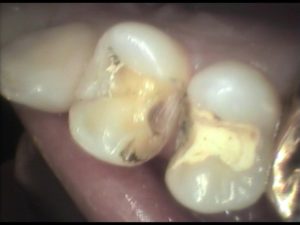

この患者さんは銀歯が外れたのですが、白い詰め物で治して欲しいとのことで来院されました。見てみると、1本金属の詰め物が外れています。手前にも金属が入っていますが、同時期に処置したものなので、近い将来同じように外れてしまう可能性が高く、一緒にやり直すことにしました。

写真のように、歯と歯の間の欠損は結構手間暇がかかります。でも小さいので2本で1時間でした。